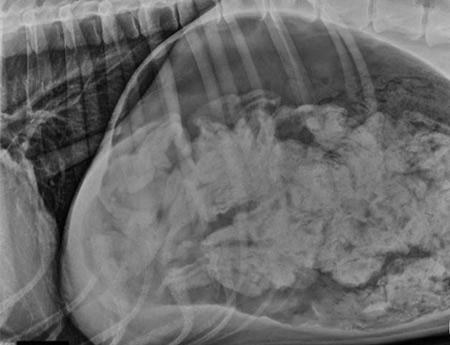

ABD’nin Oregon eyaletinde meydana gelen olayda köpeğin sahibi hayvanın inleyerek öğürmesi sonrası köpeği veterinere götürdü. Veterinerde köpeğin midesinin röntgeninin çekilmesi sonucunda gerçek ortaya çıktı. Veteriner yetkilileri köpeğin midesinde çorap olduğunu ve operasyonla hemen alınması gerektiğini ifade etti. 2 saatlik operasyon sonucunda köpeğin midesinden tam 43 çorap çıkartıldı.

Olay sonrası açıklama yapan veteriner Ashley Magee, “Köpeğin midesini açtığımızda farklı tür ve boyutlarda bir sürü çorap gördük” dedi. Magee, operasyon sonrası köpeğin durumunun iyi olduğunu ve evine gönderildiğini ifade etti.